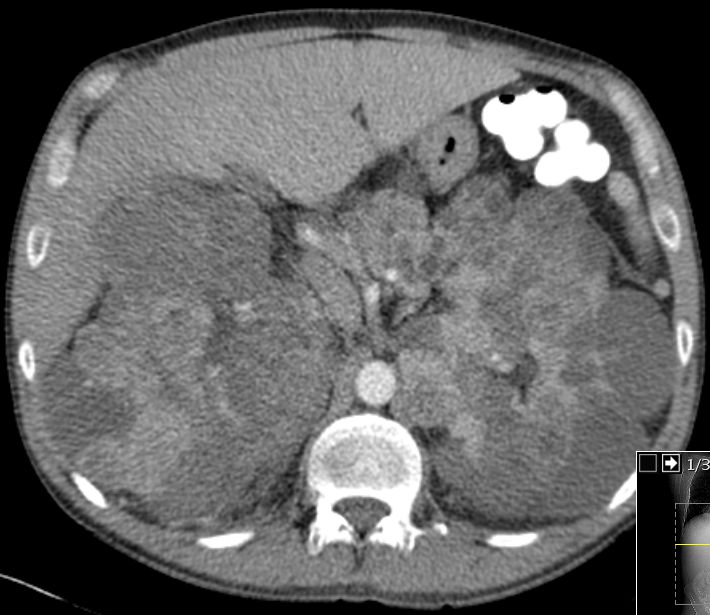

Riesige Zystennieren beiderseits.

Die Zystennieren enthielter beiderseits Nierenzellkarzinome. Die Lungenmetastasierung ist erkennbar.